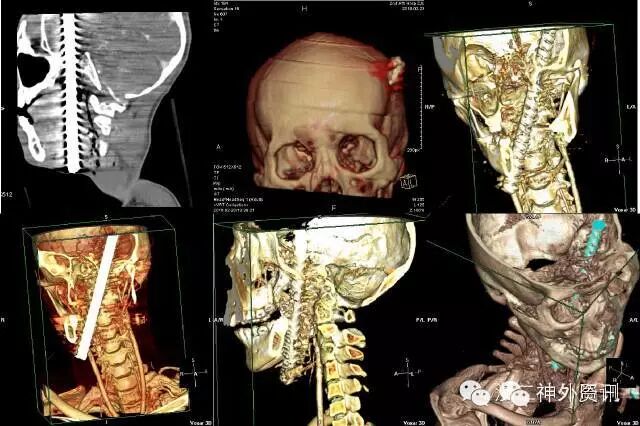

头颅CT提示:可见金属棒状物自右颈部颌下斜行经口咽、左侧鼻咽及中颅底,至左侧额颞部颅骨穿出,伴右侧颌下及上颈部皮下气肿,周边放射状伪影明显,周围结构显示欠清,左颞叶脑实质穿透,异物周边脑实质水肿,右侧脑室受压变形,局部中线结构轻度右偏。左顶部头皮软组织肿胀。左侧中颅底及左顶骨骨折,鼻骨骨折(见图2)。

图2. 头颅CT提示螺纹钢与左颈内动脉管贴近,最近处约2mm(箭头所示)。

颈动脉CTA示:两侧颈动脉周边未见明确血肿,金属异物与左颈内动脉管贴近(见图 3)。

图 3. 三维重建显示螺纹钢位置。